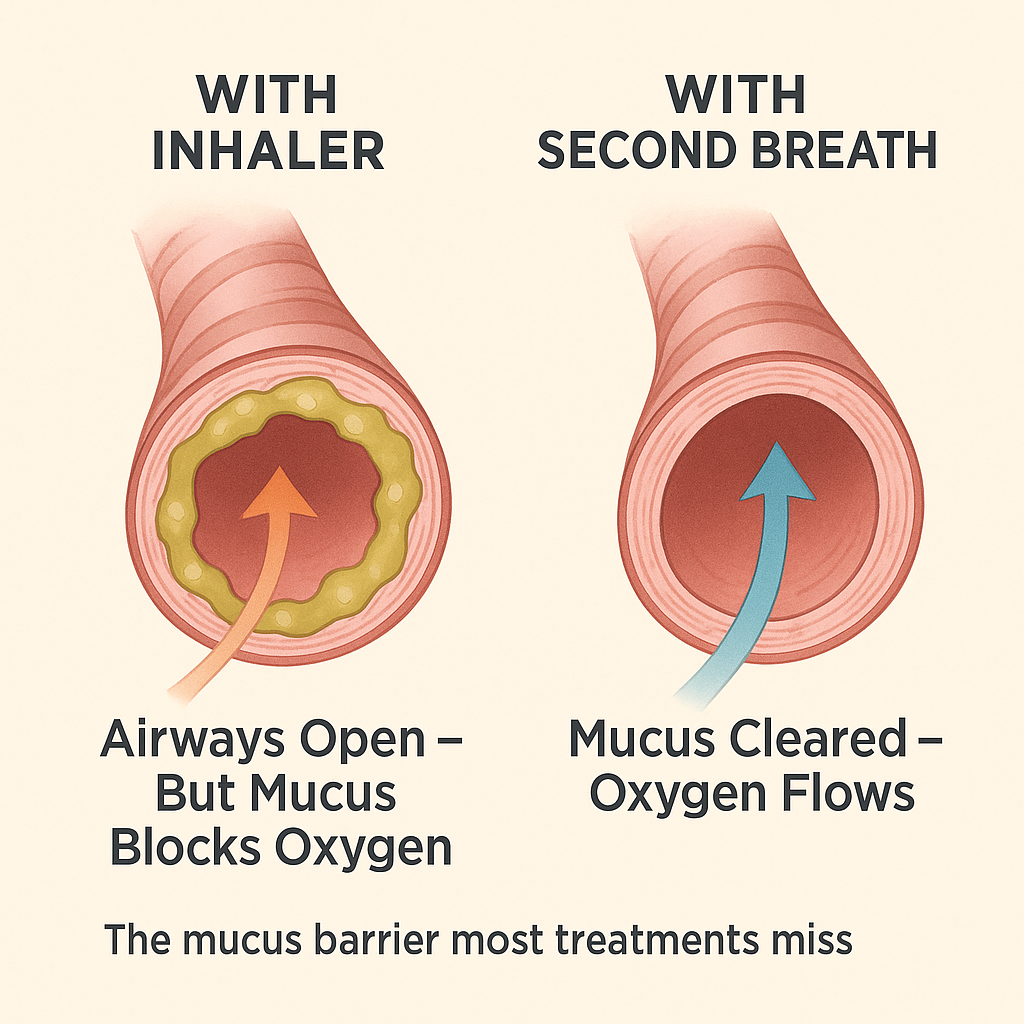

From 'Fighting for Breath' to Breathing Clearly— What Your Inhaler Can't Fix

From 'Fighting for Breath' to Breathing Clearly— What Your Inhaler Can't Fix